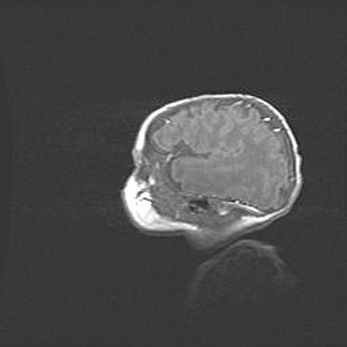

Наружная гидроцефалия с возможной атрофией височных областей.

Возраст: 28 дней

Вес: 3670 г

Пол: мужской

Окружность головы: 38 см

Срок гестации: 40 недель

Гидроцефалия головного мозга у новорожденных – это заболевание, которое характеризуется скоплением избыточного количества спинномозговой жидкости в желудочковой системе головного мозга в результате затруднения её перемещения от места выработки к месту поглощения в кровеносную систему или вследствие нарушения абсорбции. При открытой наружной форме гидроцефалии у новорожденных расширяются и переполняются субарахноидные пространства.

При нормотензивных  формах,  которые,  как  правило,  являются  следствием  перенесенных ишемических  повреждений  паренхимы  мозга,  возможно  сочетание микроцефалии  с нормотензивной гидроцефалией. В основе данных изменений лежит атрофия больших полушарий с преимущественной  локализацией  в  лобно-височных  областях.